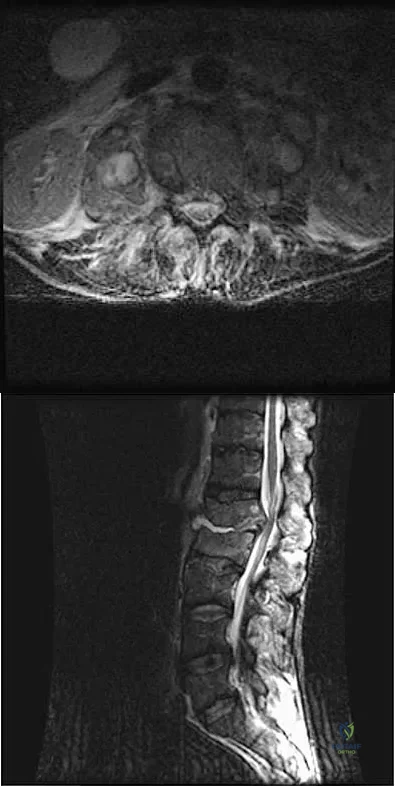

A 32-year-old man notes increasing back pain and progressive paraparesis over the past few weeks. He is febrile, and laboratory studies show a WBC of 12,500/mm3. MRI scans are shown in Figures 6a and 6b. Management should consist of

Explanation